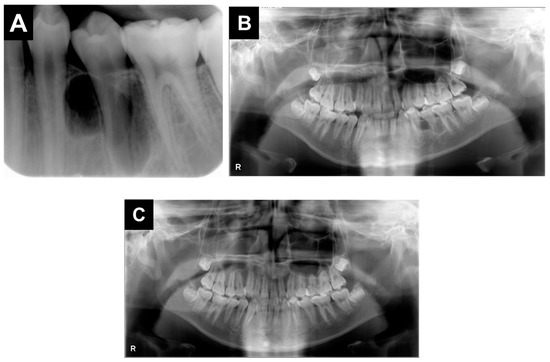

2. Case Report